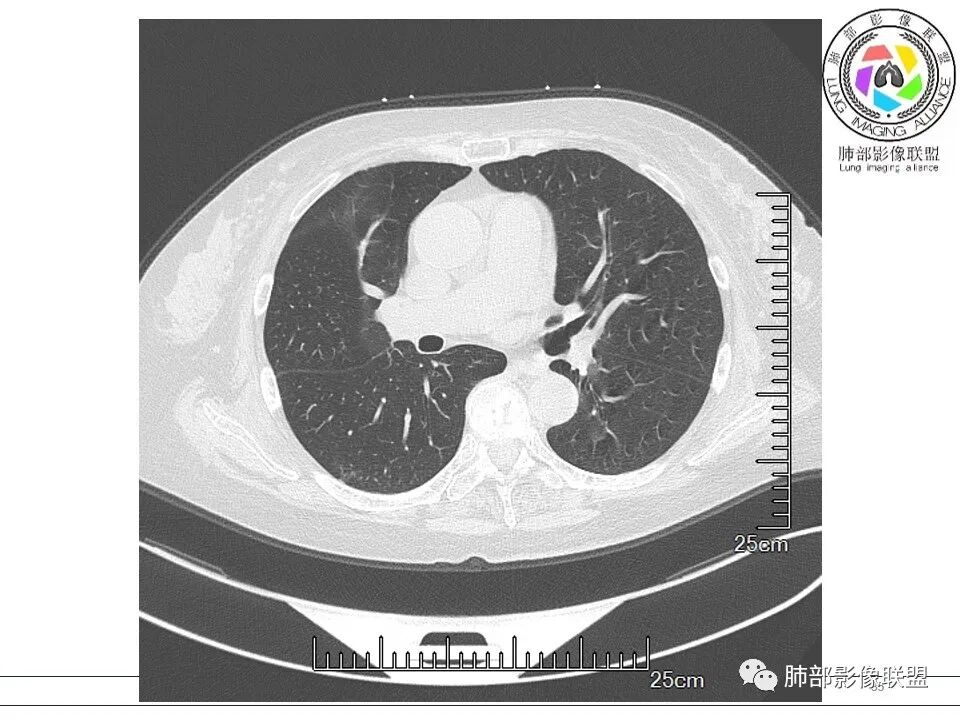

玫: 晨读:右肺上叶胸膜下软组织密度影,边缘模糊,周围见条索影及少许磨玻璃影,轻度胸膜牵拉,考虑炎性病变。

金豆 (刘权威): 右肺上叶胸膜下团块,支气管充气征,边缘纤维索条,磨玻璃,OP。

瑞欣 (刑瑞欣): 晨读,老年女性,右肺上叶不规则高密度影,可见胸膜牵拉,边缘光滑平直,与胸膜平行,周围条状影,可见支气管充气征,有风湿病史,考虑机化性炎症,鉴别隐球菌,腺癌

良孑: 右肺胸膜下多发结节,长轴与胸膜平行,部分病灶有多结节融合,可见近端支气管充气征,有晕征及晕中软毛刺,长期口服激素病史,抗炎效果欠佳。病灶形态单一,无播散性树芽,结节内无支气管穿行,单侧发病,收缩力差,可排除TB,OP及淋巴瘤,综和考虑支持隐球菌

尘缘: 典型的隐球机化期改变

尘缘: 先抗隐球,如果还有机化没改变,再激素

南边: 我见过几例,有些是开始误诊,一直单纯抗炎,每次穿刺都是OP,影像上就是隐球的表现,很典型,确实没抗真菌。我看结核也有类似的问题,有一些病号就是以OP为主阶段,我都怀疑,类郝氏反应其实就是机化导致的,不是病原菌直接导致的。我个人观点:SOP

尘缘: 这种要看隐球荚膜抗原和Ngs检查结果,如果明确有隐球存在,要么抗真菌,要么不治疗,也肯定不敢直接激素抗机化,否则,出了问题就自找麻烦

南边: 目前都认为各种病因所致后期的机化改变,我想结核、隐球菌等特殊感染都可以,后来都是抗机化,只是没查到病原菌而已,而不是针对性抗病原菌,这阶段我认为病原菌是被身体本身的免疫系统压制住,或者消灭了,只是后期的炎性反应所致的副作用导致的临床症状,影像表现其实很大一部分的隐球菌都误诊或者漏诊了,反正都好了。